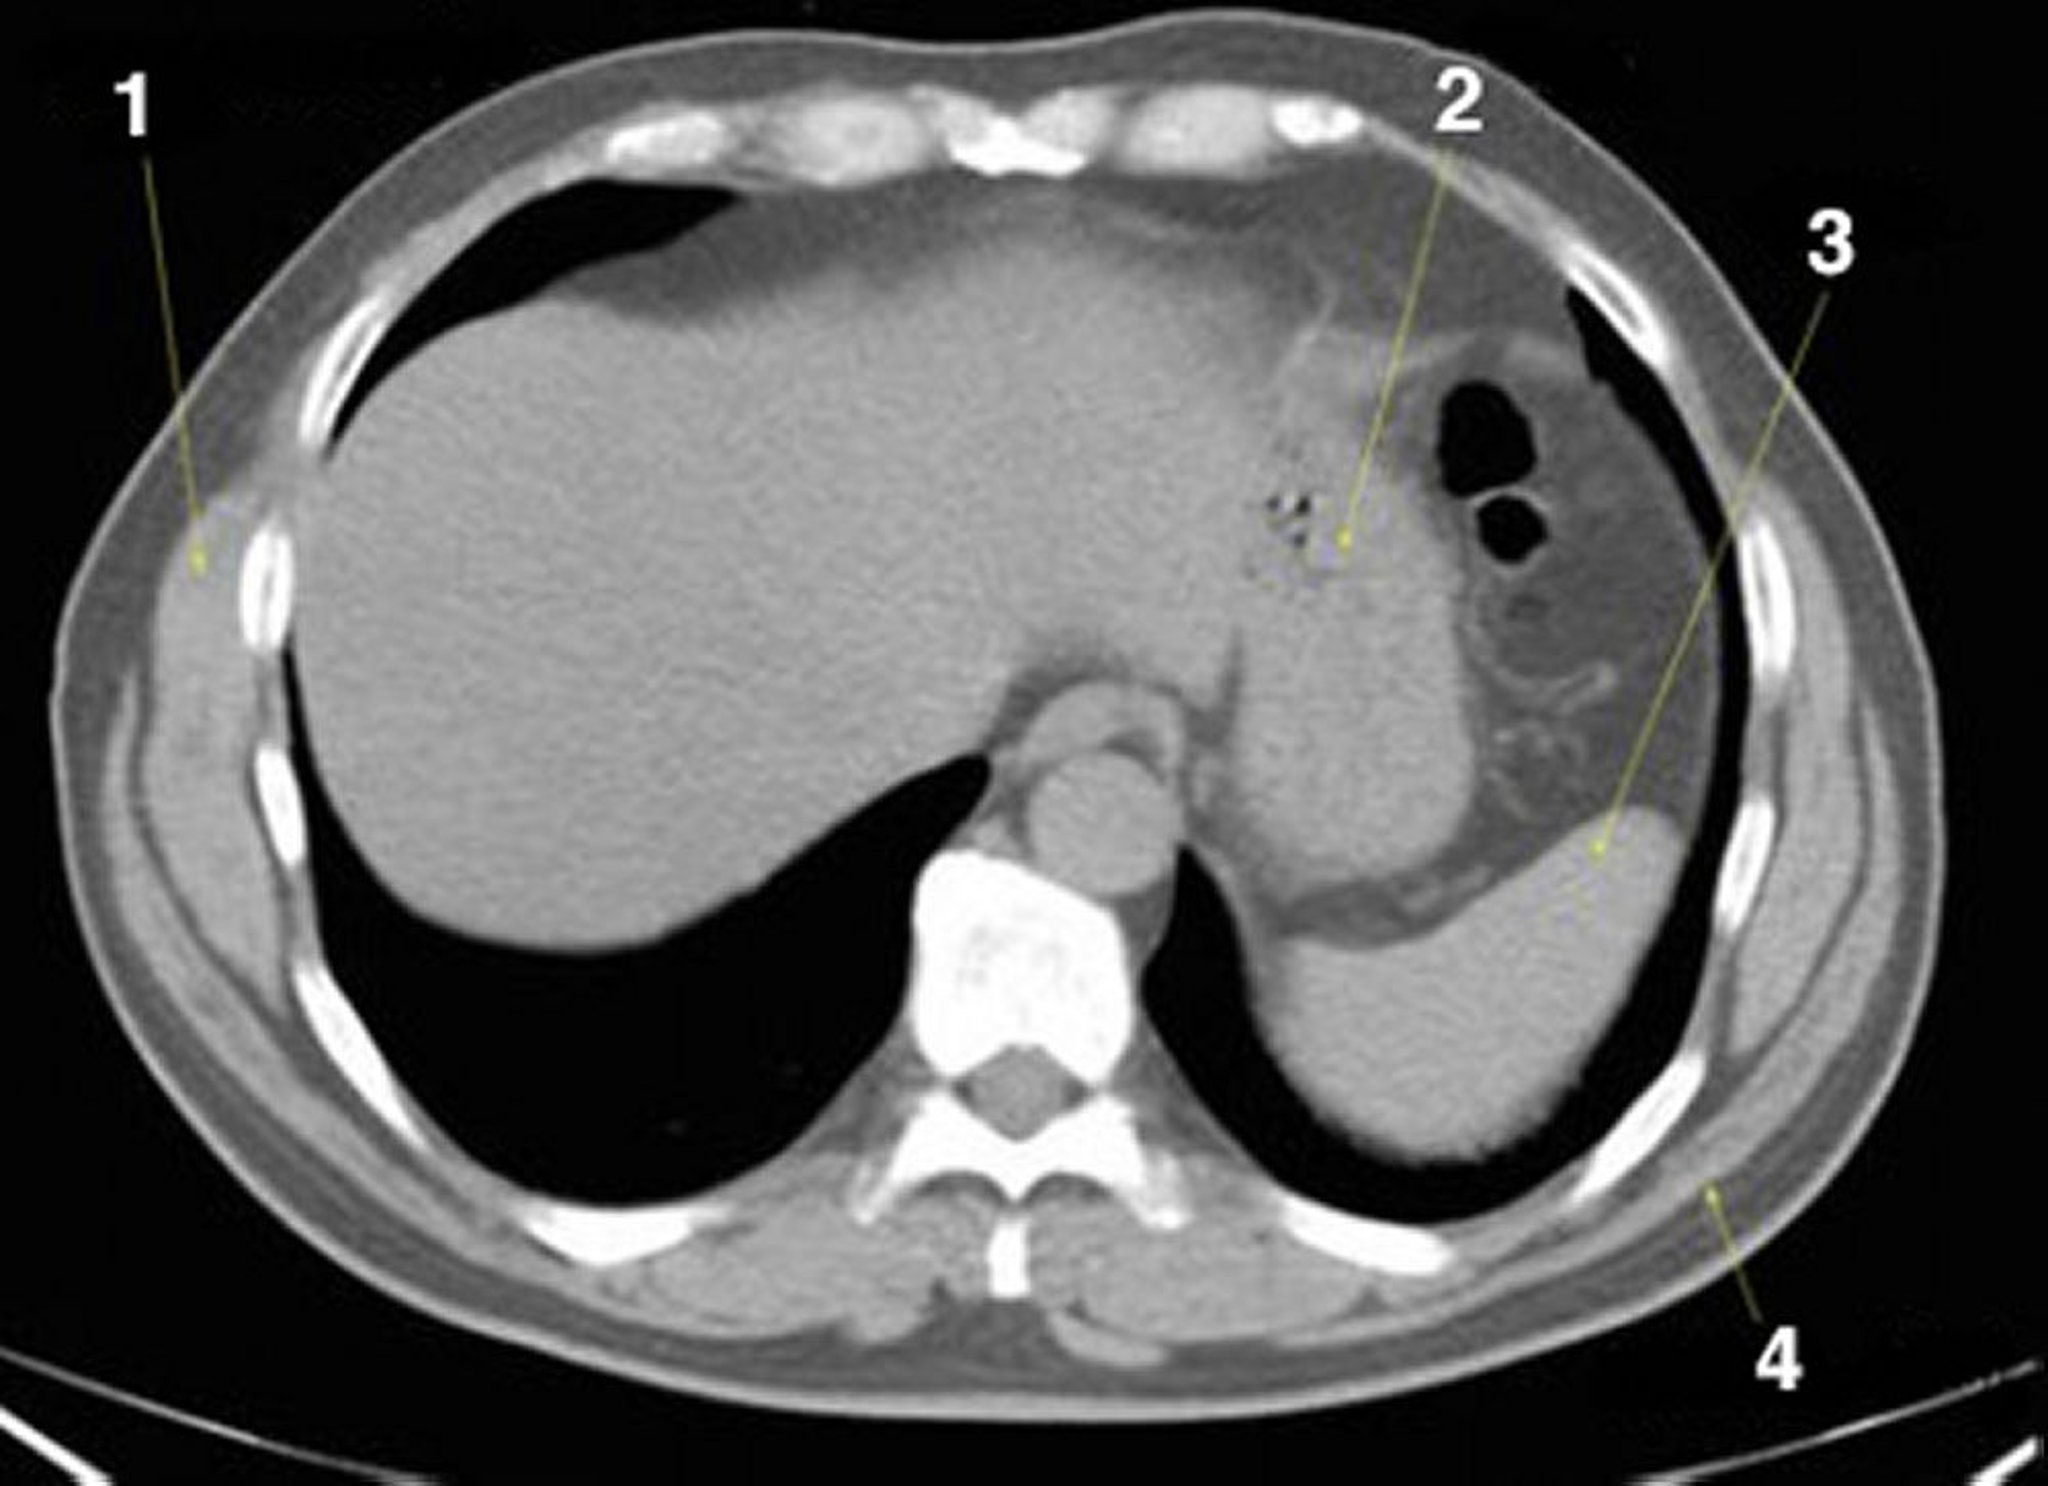

CT-Scan von Abdomen und Becken mit normaler Anatomie ohne Kontrastmittel (Folie 2)

1 = M. serratus anterior; 2 = Magen; 3 = Milz; 4 = M. latissimus dorsi.